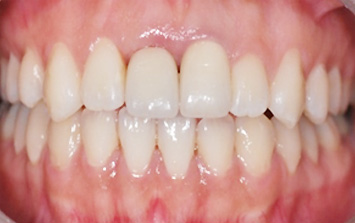

앞니 상실과 보철물 오염으로 내원한 환자분. 오른쪽 오염된 보철물로 인하여 잇몸이 올라간 상태, 치주치료와 올세라믹 치료를 하고

상실된 부위에 임플란트를 식립 하였습니다. 앞니의 경우 외모를 결정시키는 중요한 의미가 있기 때문에

자연치아와 구별 안될 정도로 자연스럽게 만들어 드렸습니다.